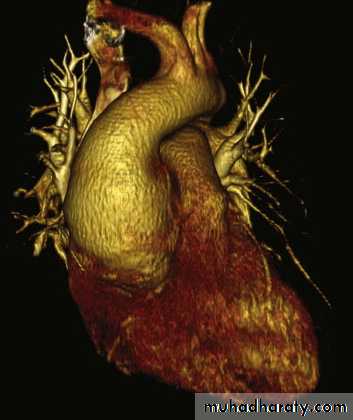

Three-dimensional abdominal CT showing abdominal aortic aneurysm